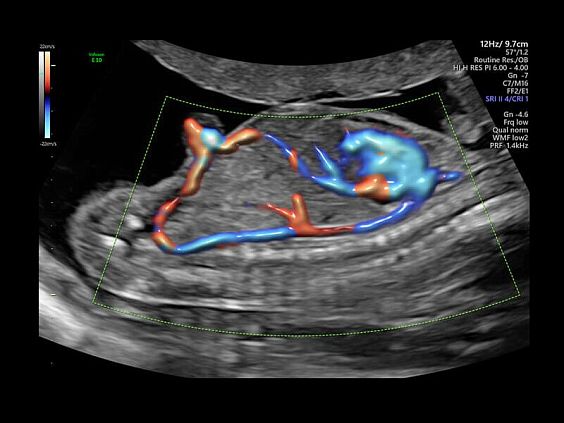

• Реалистичный объёмный кровоток в режиме ЦДК (Radiantflow)

• HDlive Flow - перемещаемый источник света, совместимый с визуализацией кровотока в 3D

• HDlive Flow Silhouette - режим "Силуэт" с выделением границ полостей сердца и сосудов, совместимый с визуализацией кровотока

• Технология HDlive Flow — повышает реалистичность визуализации сосудистых структур, улучшая восприятие глубины (по сравнению с традиционным цветовым допплером и функцией HD-Flow).